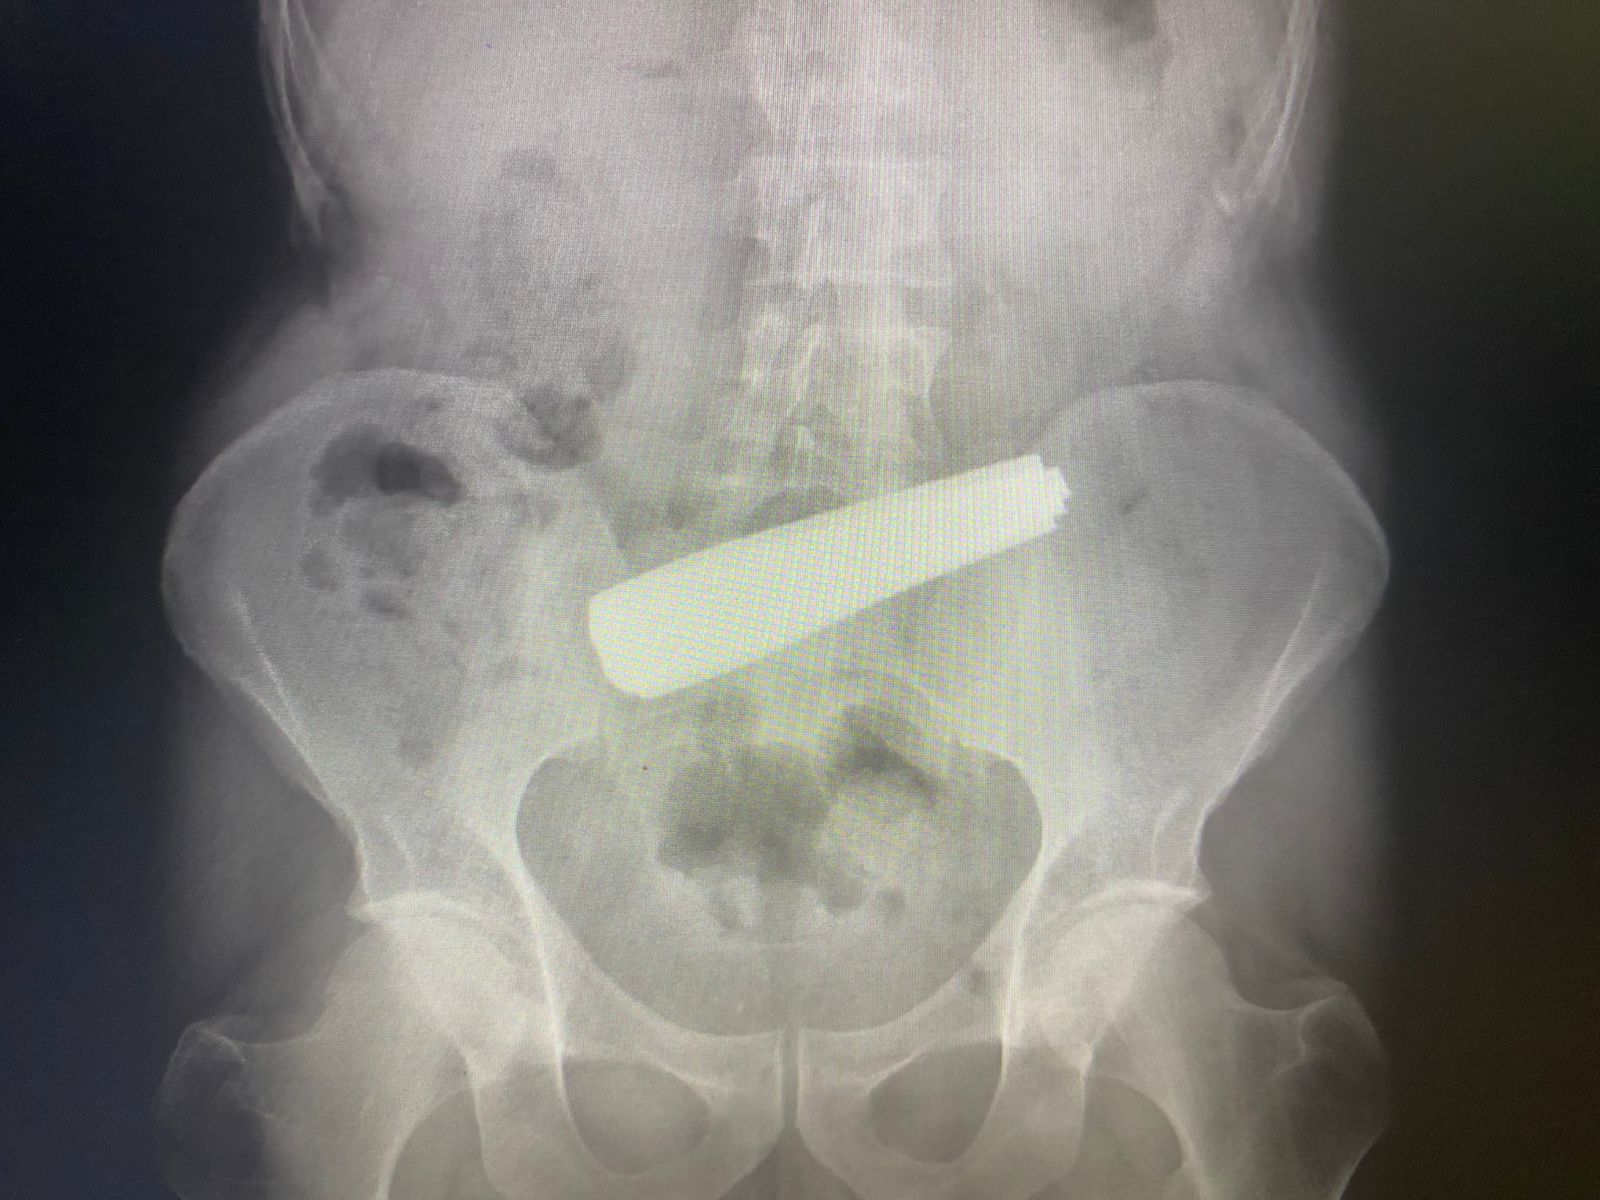

Больной проглотил аж девять чайных ложек, однако предварительно сломал их пополам, чтобы легче было глотать. Об этом Minval сообщили в Бакинском центре здоровья.

По данным, пациент поступил в медицинское учреждение в первом часу утра 19 мая. Его в тяжелом состояние перевели в Бакинский центр здоровья из Клинического медицинского центра №3. Никакая другая больница не бралась оперировать больного, однако врачи Бакинского центра здоровья справились с этой сложной задачей и в течение 7 часов эндоскопическим способом извлекли из незадачливого пациента все части столовых приборов.